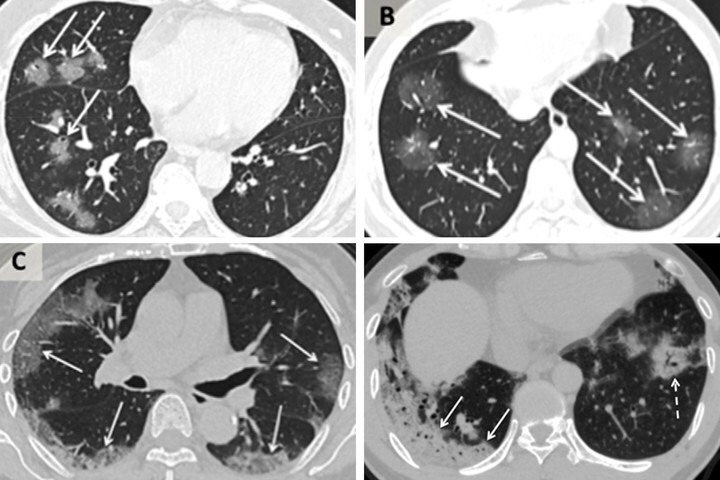

Una vez dentro del cuerpo del huésped las partículas virales viajan rápidamente al fondo de los conductos nasales y las mucosas del fondo de la garganta. Allí los síntomas comienzan con dolor y tos seca pero conforme las copias del virus empiezan a multiplicarse infectan a las células vecinas y el virus desciende progresivamente por los conductos bronquiales. Al llegar a los pulmones ataca a las membranas mucosas inflamándolas y dañando los alvéolos que suministran oxígeno a la sangre produciéndose una inflamación que dificulta que el oxígeno se intercambie a través de la membrana mucosa con lo que los pulmones empiezan a llenarse de fluidos, pus y células muertas y aparece la neumonía.

Los síntomas de COVID-19 pueden ser desde moderados a graves. Según la OMS, alrededor del 15% de los casos son graves y el 5% son críticos. En los más lesivos las personas tienen tanta dificultad para respirar que necesitan que se les coloque un respirador y en los peores casos, conocidos como Síndrome de Dificultad Respiratoria Aguda, los pulmones de los afectados se llenan de tanta cantidad de fluidos que ningún apoyo respiratorio es suficiente y el paciente muere.

Tomografías computarizadas de pacientes chinos con coronavirus. Fuente: Clarin